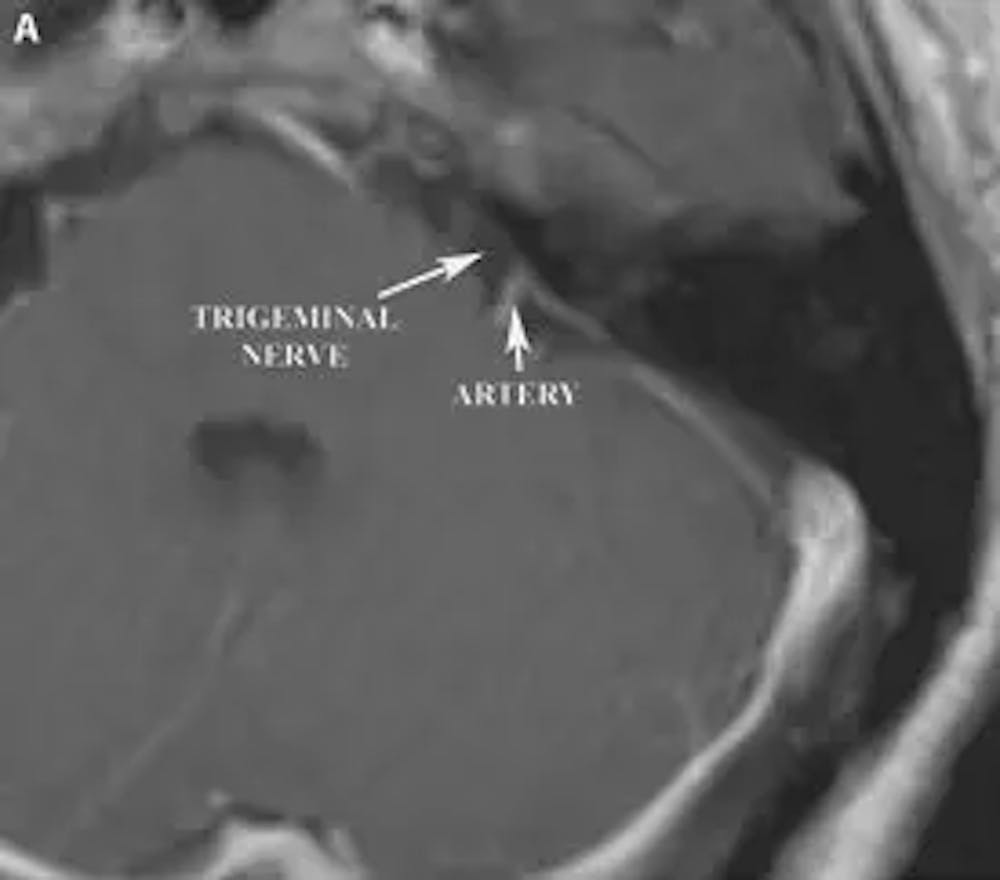

A) Pre-operative axial T1 weighted MRI of the brain with contrast demonstrating proximity of a loop of the superior cerebellar artery to the trigeminal nerve.

Trigeminal neuralgia, in most cases, is caused when a blood vessel compresses the trigeminal nerve as it exits the brain stem. Rarely tumors, cysts, or vascular malformations can compress the trigeminal nerve as it exits the brain stem, causing lancinating facial pain. Multiple sclerosis affecting the brain stem can also cause trigeminal neuralgia.

The primary surgical treatment for trigeminal neuralgia involves exposing the facial nerve as it exits the brainstem and identifying the blood vessel that is compressing the nerve. This blood vessel is then separated from the nerve using a piece of Teflon felt. This procedure, called a microvascular decompression (MVD), may result in pain relief for a period of 10 years or more in 70 percent of patients.